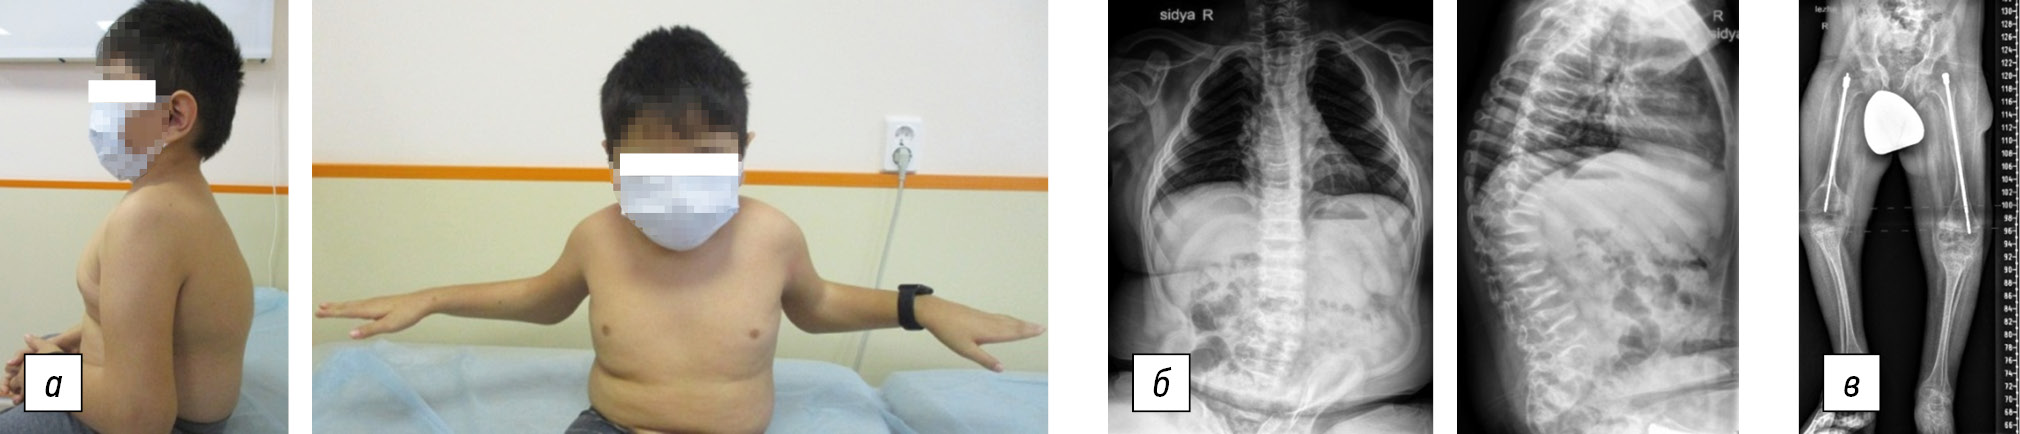

Fig. 4. Patient I, 10 years old, Bruck syndrome type 2: a, general view of the patient; b, anteroposterior and lateral projection radiographs of the spine: local pathologic kyphosis in the thoracic region, 45° with decreased height and wedge-shaped vertebral bodies, hyperlordosis in the lumbar region, and 26° left-sided scoliotic arch in the thoracolumbar region; c, panoramic radiograph of the lower extremities in the anteroposterior projection: intramedullary fixation of the femurs with telescopic rods

The boy is currently 10 years old and can sit independently but cannot walk. He has a height of 116 cm and a brachycephalic head. His face is symmetrical with protruding frontal tubercles, and his neck is short. The spinal axis is curved in the sagittal plane. Specifically, the cervical region is straight; local kyphosis in the thoracolumbar transition area and hyperlordosis in the lumbar region are noted. Additionally, a left-sided scoliotic deformity is determined in the thoracolumbar region. The length of the upper limbs is equal, and there are no limitations in the movements of the shoulder joints. There is a 40° flexion deficit in the right elbow joint and a 50° flexion deficit in the left elbow joint. Hand function is not impaired. The left lower limb is relatively short by 2.5 cm. Flexion contractures of the hip joints with a deficit of extension of 40° and flexion up to 60° on both sides were noted, as well as flexion contractures of the knee joints with a deficit of extension of 50° and flexion up to 80° on both sides. Additionally, an equinovalgus deformity of both feet was observed.

Radiographs of the spine in frontal and lateral projections revealed local pathologic kyphosis in the thoracic region of 45°, platyspondylia, wedge-shaped vertebral bodies, hyperlordosis in the lumbar region, and a left-sided scoliotic arch in the thoracolumbar region of 26° (Fig. 4). Table 2 presents the densitometry data. The observation period revealed pronounced vitamin D deficiency (level: 12 ng/mL; normal range: 30–80 ng/mL). Additionally, increased levels of C-terminal telopeptide (up to 2.6 ng/mL; normal: 1.63–1.94 ng/mL) and N-terminal propeptide (1037 ng/mL at the beginning of treatment; 649 ng/mL at present; normal: 388–571.6 ng/mL) persisted. However, all other indices of bone tissue metabolism, including calcium, phosphorus, alkaline phosphatase, osteocalcin, and parathormone, were within normal limits.